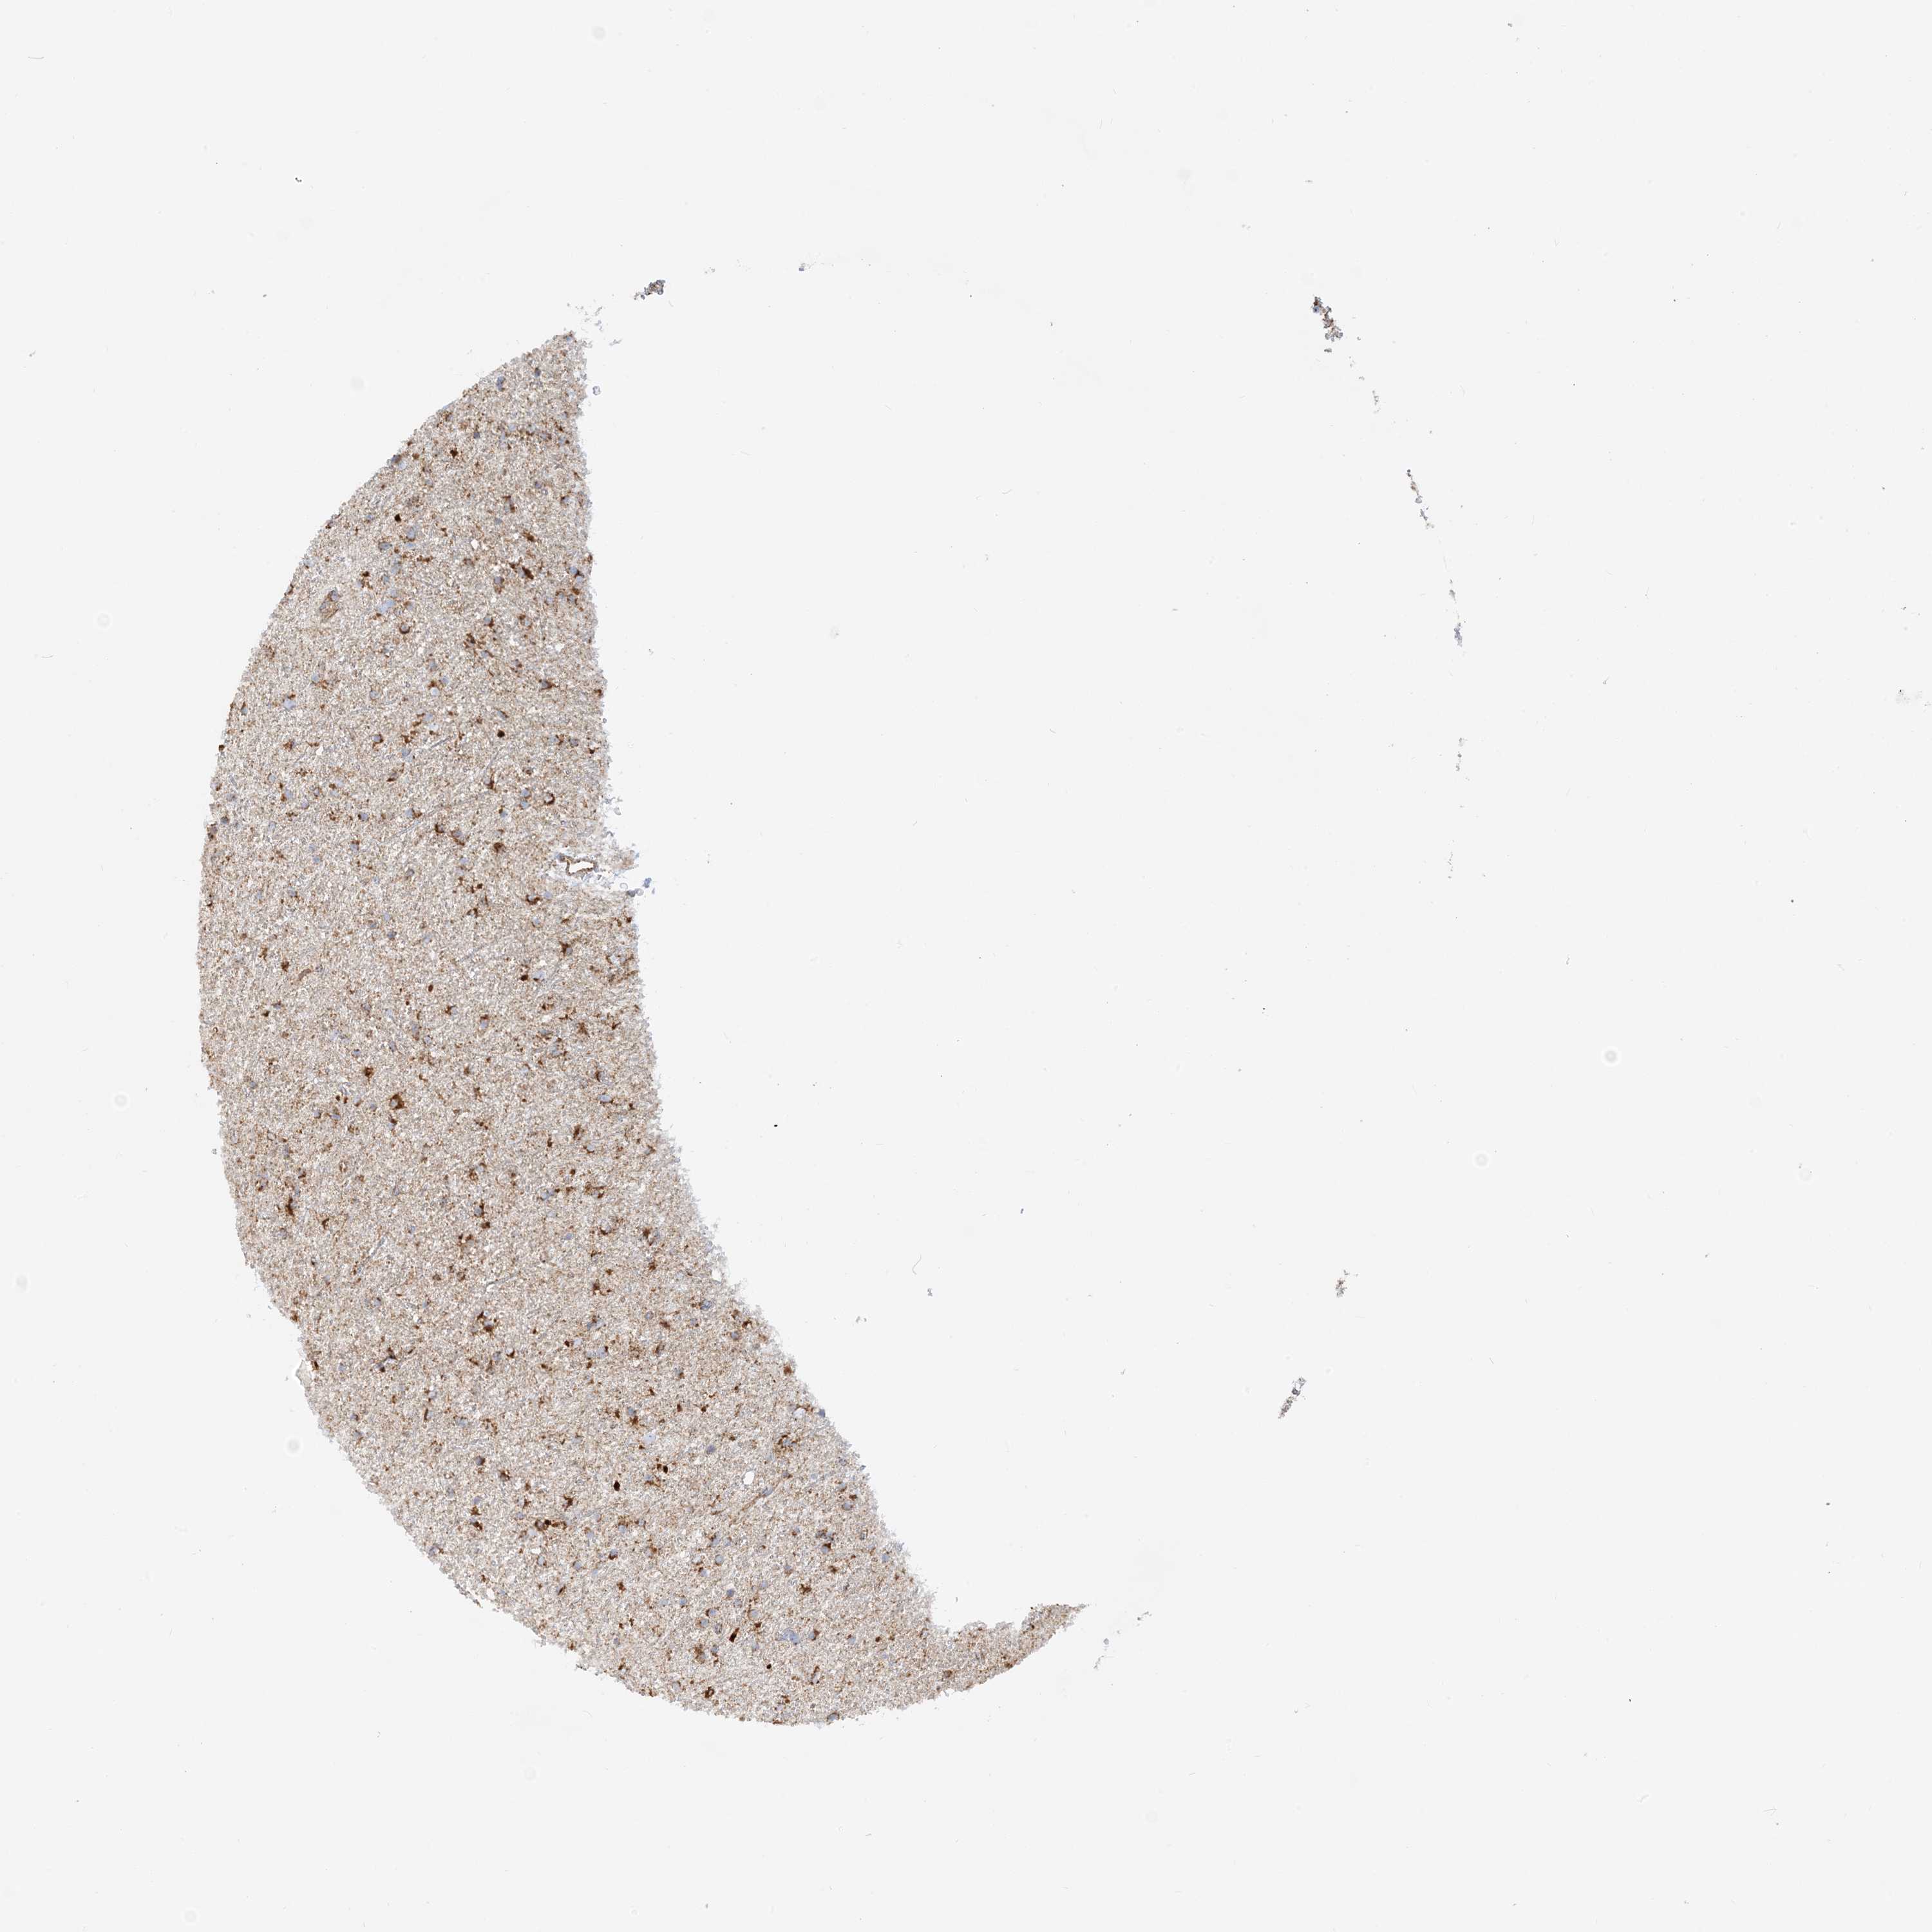

GLIOMA - Protein expressioni

A mouse-over function shows sample information and annotation data. Click on an image to view it in a full screen mode. Samples can be filtered based on level of antibody staining by selecting one or several of the following categories: high, medium, low and not detected. The assay and annotation is described here.

Note that samples used for immunohistochemistry by the Human Protein Atlas do not correspond to samples in the TCGA dataset.

Antibody stainingi

Antibody staining in the annotated cell types in the current human tissue is reported as not detected, low, medium, or high, based on conventional immunohistochemistry profiling in selected tissues. This score is based on the combination of the staining intensity and fraction of stained cells.

Each image is clickable and will lead to virtual microscopy that enables deeper exploration of all samples and also displays staining intensity scores, fraction scores and subcellular localization as well as patient and tissue information for each sample.

Antibody HPA031966

Staining

High

Medium

Low

Not detected

Intensity

Strong

Moderate

Weak

Negative

Quantity

>75%

75%-25%

<25%

None

Location

Nuclear

Cytoplasmic/membranous

Cytoplasmic/membranous,nuclear

Glioma, malignant, High grade

Glioma, malignant, Low grade

Glioblastoma, NOS